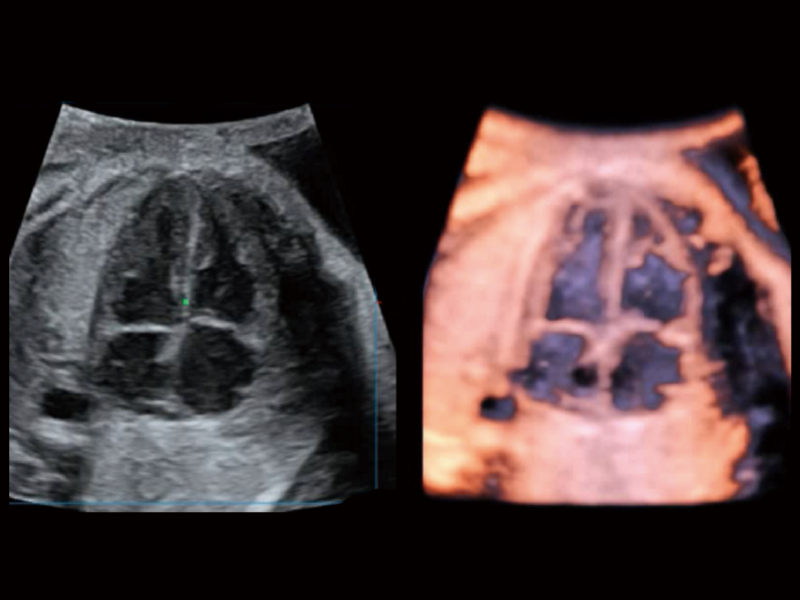

豐富的血流動(dòng)力學(xué)檢測(cè)技術(shù),可在不同醫(yī)療場(chǎng)景中高效捕捉血流信號(hào),助力臨床診療。

在傳統(tǒng)血流的基礎(chǔ)上優(yōu)化掃查和算法策略,能夠更好的抑制組織信息,提煉紅細(xì)胞運(yùn)動(dòng)信息,得到更高幀頻,高靈敏度和分辨率的血流信號(hào),還原更真實(shí)的血流動(dòng)力學(xué)。

通過光照模型,使二維血流顯示出立體的效果,增加血流的敏感性、成束性,減少外溢??梢院推渌煌难骷夹g(shù)聯(lián)合使用,融合不同技術(shù)的優(yōu)勢(shì)。輕松應(yīng)對(duì)微小血管,增強(qiáng)血流的立體效果,提升視覺敏感性。

通過創(chuàng)新的Matrix E自適應(yīng)濾波算法,能有效濾除軟組織和噪聲信號(hào),最大限度保留超低速微細(xì)血流的信號(hào);結(jié)合超長時(shí)間域算法,極大提升細(xì)微血流的敏感性和空間分辨率,更真實(shí)的反應(yīng)組織、包塊的血流灌注情況。